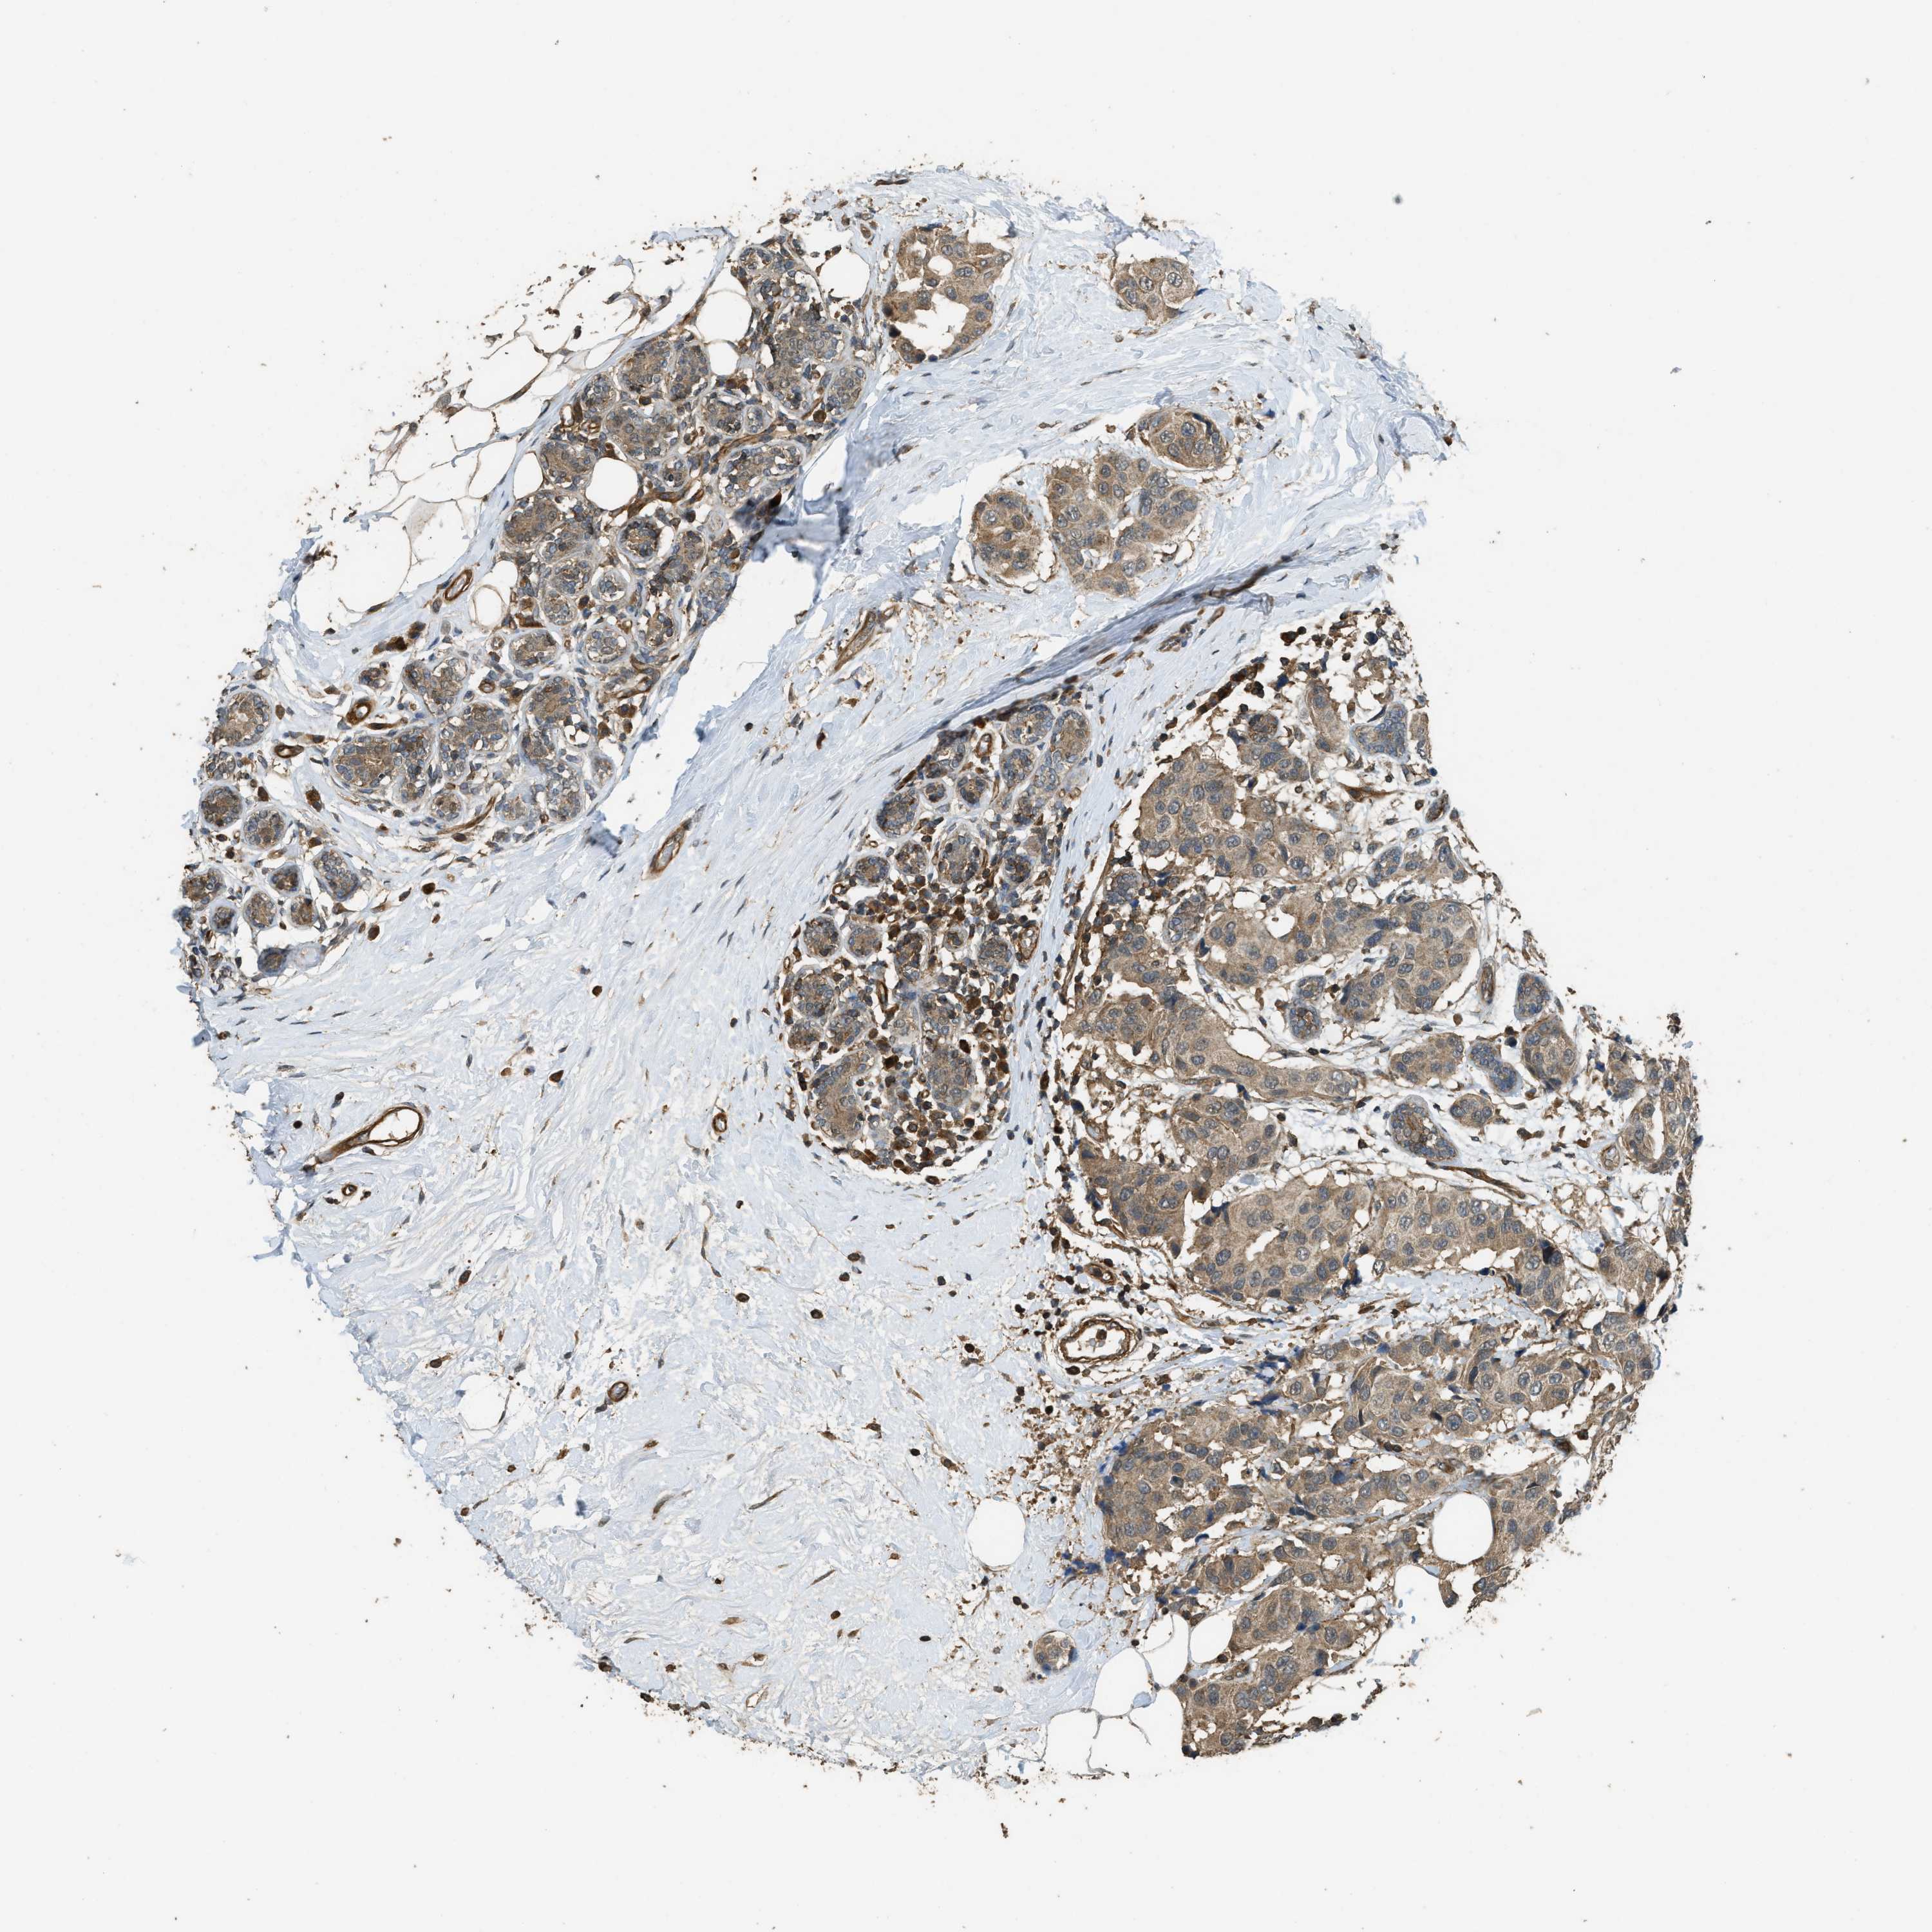

CANCER BREAST CANCER Show tissue menu

BRCA TCGA BRCA VALIDATION PROTEIN EXPRESSION